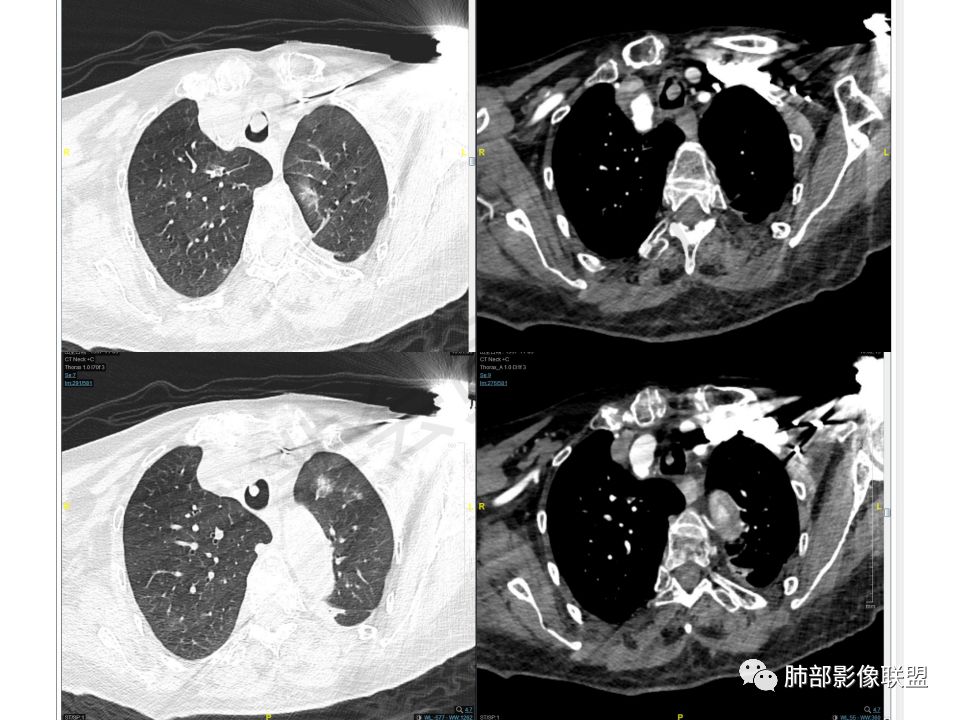

老年女性,间断咯血两年。影像:气管内带蒂结节,边缘光滑明显强化。左肺下叶背段支气管截断,远端不张。两肺散在大小不等结节及磨玻璃影,明显强化,磨玻璃影考虑合并出血可能。纵隔多发淋巴结肿大,两侧支气管受压。综合考虑:肺癌伴两肺转移。原发气管结节还是左肺下叶背段?腺样囊性癌?类癌?

气管占位,两肺多发肿块,左下肺不张。

气管占位与肺内肿块血供异常丰富,接近大动脉强化,可以考虑同源

主支气管上段及中下段分叉内结节,部分气管壁间隙可见,明显强化,和双肺多发结节强化差异不大,考虑转移?。

老年女性,气管腔内占位,左肺下叶阻塞性炎症伴不张,腔外病灶大于腔内,左肺门血管包埋,外缘欠光滑,似有冰山征。纵隔淋巴结,双肺多发富血供团块样转移结节。

气管黏膜下肿块,气管软骨完整,增强后明显强化!双肺多发结节肿块,明显强化,边缘光整,与气管强化相仿,考虑同源,均考虑转移,老年女性,富血供转移,软组织肉瘤?甲状腺癌?

晨读:老年女性,间断咯血2年,呼吸困难2月,加重3天,高血压冠心病史40余年,阵发性房颤20余年,老年痴呆10年,贫血5年,气管腔内不规则结节,强化明显,双肺多发圆形或类圆形结节,强化明显。临床症状病史加影像改变综合分析,有三种可能:1、气管原发恶性肿瘤伴肺内转移,2、气管与肺部均为富血供转移,原发待定,3、气管内良性肿瘤性结节,肺内恶性转移。个人倾向于气管类癌或非典型类癌合并肺上转移,并类癌综合征可能,其他两个可能待鉴别,建议查甲状腺,腹部CT,肿瘤标志物。

气管腔内占位,强化异常明显,窄基底与粘膜相连,还是带蒂?

两肺结节胸膜下,边缘光滑,强化与气管内病灶一致